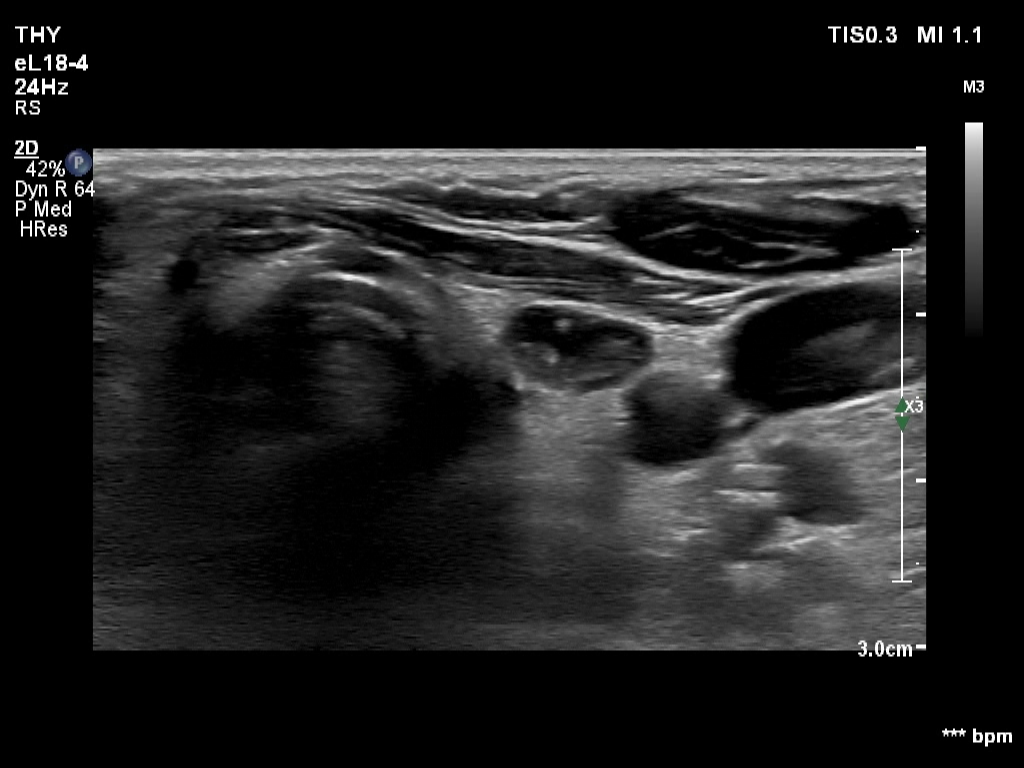

Right lobe, longitudinal scan

Left lobe, another transverse view - with better harmonization. The ventral half of the node seems to be deceptively cystic.